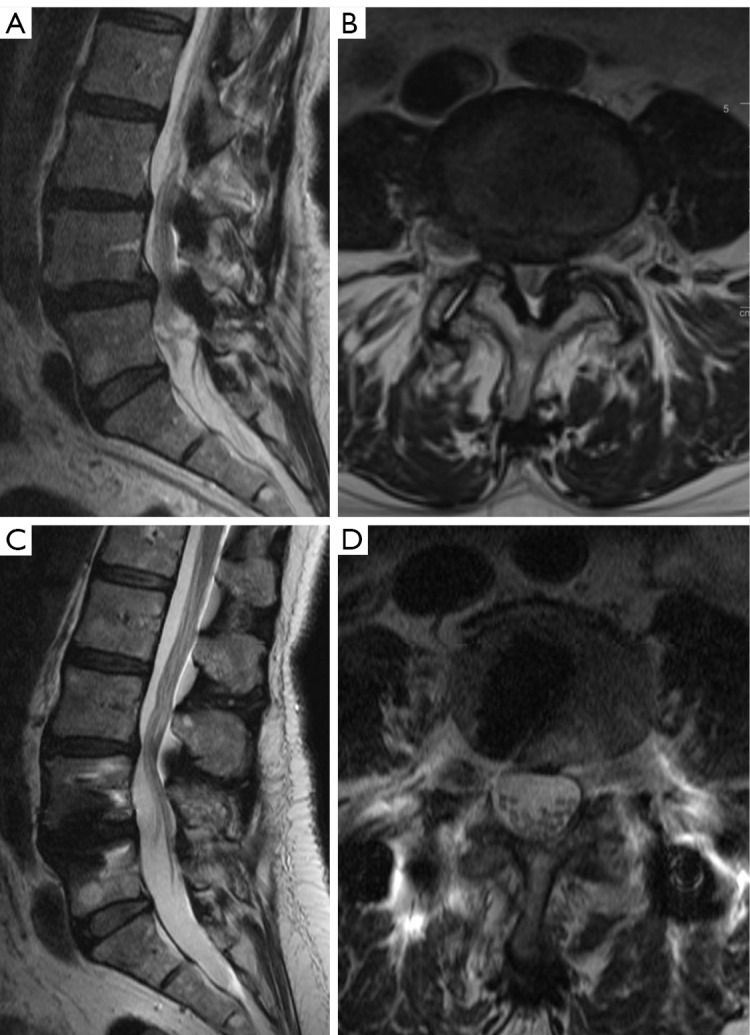

Short-term clinical and radiographic results of expandable cages that expand both height and lordosis for minimally invasive transforaminal lumbar interbody fusion (MIS TLIF).

在微创经椎间孔腰椎体间融合术(MIS TLIF)中扩展高度和前凸的可扩展固定架的短期临床和影像学结果。